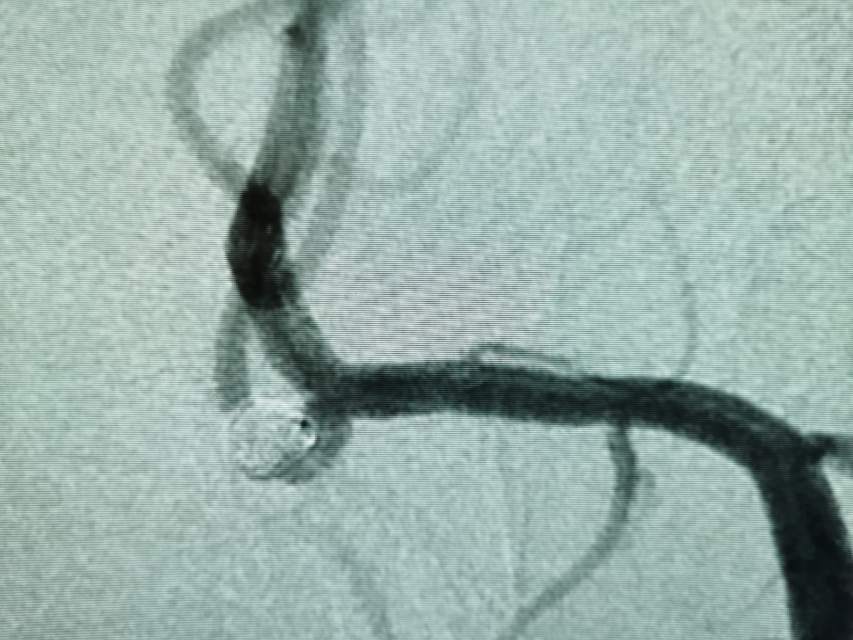

本次复查左侧栓塞的动脉瘤,不显影